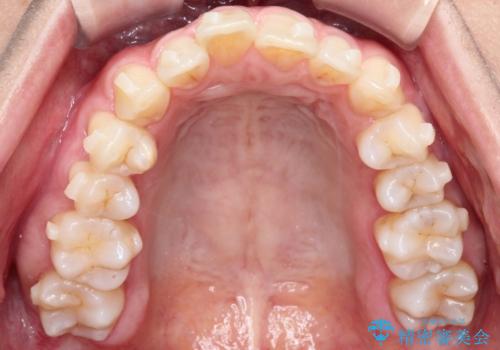

【インビザライン】前歯の凸凹を治したい

- 前歯の凸凹を主訴に来院されました。

臼歯部の遠心移動を行いながらスペースを作り、インビザラインにて前歯をきれいに並べることができました。

今回の治療計画では臼歯部の遠心移動とIPRを行っています。